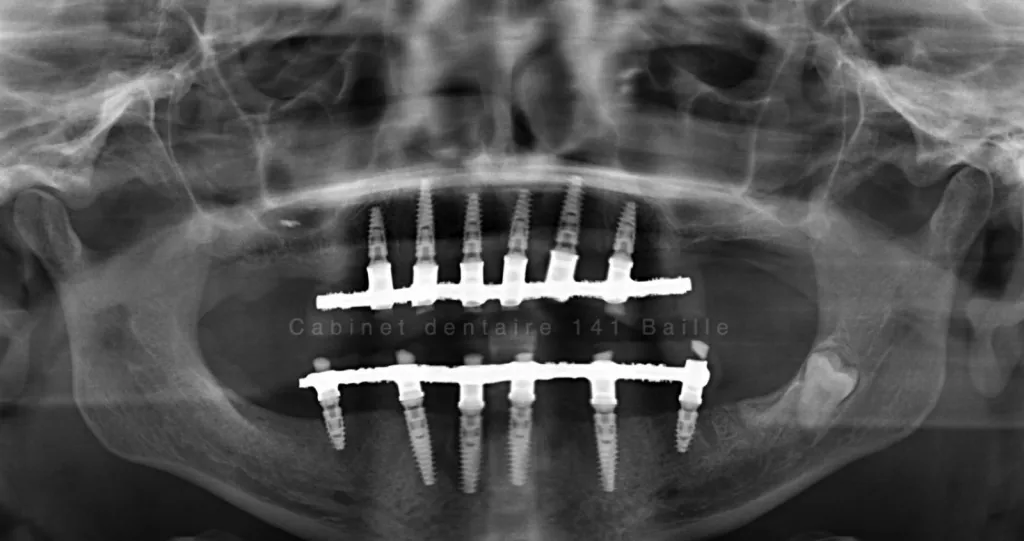

Nous sommes en mesure d'assurer la prise en charge de vos patients dans notre structure qui englobe la phase chirurgicale traitée naturellement en bloc opératoire stérile ,et sytème de traçabilité chirugicale aux normes hospitalières (Cycles prions à fractionnement de vide) ,pour tous les cas complexes intégrant implantations totales avec mise en charge immédiate.

Notre laboratoire intégré nous délivrera une prothèse immédiate qui permettra à votre patient de na pas avoir de gêne au niveau de sa vie sociale.

En général nous commençons à opérer le matin vers 9 h et la patient rentre chez lui vers 13h équipé d'une prothèse immédiate implanto- portée.